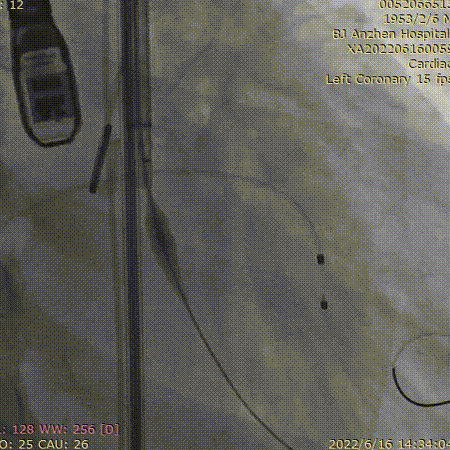

宋光远(右二)团队手术中

13点15分,前一台TAVR手术刚顺利结束,患者随即进入导管室,此时患者血压为84/56mmHg、心率105次/分。病情紧急,麻醉科医师李书闻、王建愉凭借过硬功底,快速完成桡动脉穿刺测压、深静脉置管、诱导麻醉及气管插管;超声科张纯主任送入食道超声进行细致检查;导管室付佳清护士长带领护士李想、韩立红,技师徐卫星同时完成了监护、导尿、仪器术前准备;介入医师进行消毒、器械准备以及瓣膜装配;ECMO小组也已经完成准备工作。